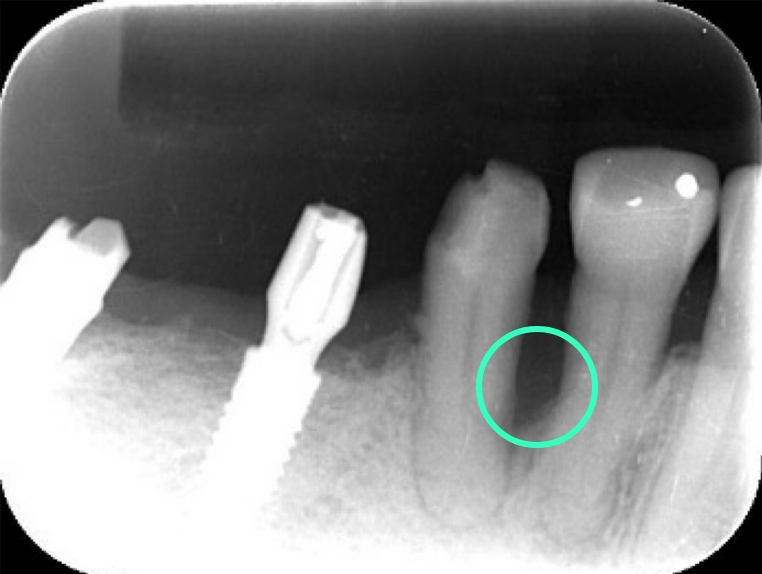

特に噛み合わせの変化は、歯根破折(歯の根が竹を割ったように割れてしまうこと)と歯を支えている歯槽骨の垂直的な吸収を引き起こしますが、噛み合わせの変化は緩やかに進行するため、自覚症状はほとんどありません。さらにこの特異な咬合状態が続くと、歯周病菌の影響で歯槽骨の垂直性吸収が起こり、破壊された骨は膿となって歯肉の中に溜まっていきます。その結果、歯肉が急に腫れ、噛むと痛みが出てくる (咬合痛)事態へと発展していきます。レントゲンでは歯槽骨の吸収が顕著に見えます。(レントゲン写真参照)

このような場合、歯周ポケットは5mm以上になってしまうことが多く、従来は歯肉を切り開いて患部の清掃をするフラッペ手術(歯周外科手術)を選択するのが常識でした。しかし、歯肉に外科的侵襲が加えられることになるので、創傷治癒には一定の時間がかかるというデメリットがあります。